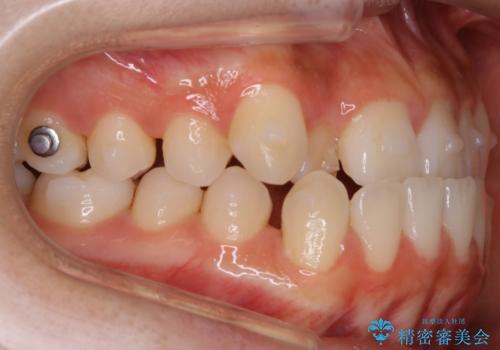

【非抜歯】受け口の改善 10代で始める本格的噛み合わせ治療

- 受け口の改善と前歯のガタつきの治療を主訴にご来院されました。

こちらの患者様の場合、上の前歯のガタつきが原因で口を閉じる際に上下の前歯の先端同士が先に当たってしまい、そこからさらに深く噛み込もうとすると下顎が前にずれていってしまうという、機能性の反対咬合であることが検査の結果わかりました。

そのため、まずは上顎の前歯のガタつきを改善していき、前歯が先に当たってしまうという症状を改善し噛み込む位置を後方の本来の位置に誘導する方法をとりました。